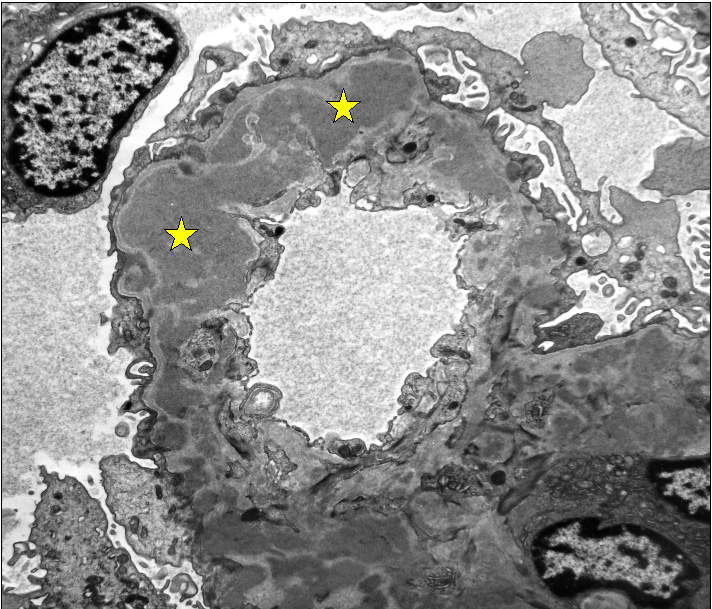

Proliferative lupus nephritis (type IV) – electron micrograph showing confluent subendothelial immune complex deposits (stars).